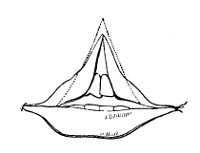

is here shown upon a scale, the squares of which are 1/4000 of an

with acetic acid. The appearance of the pus globules and molecules